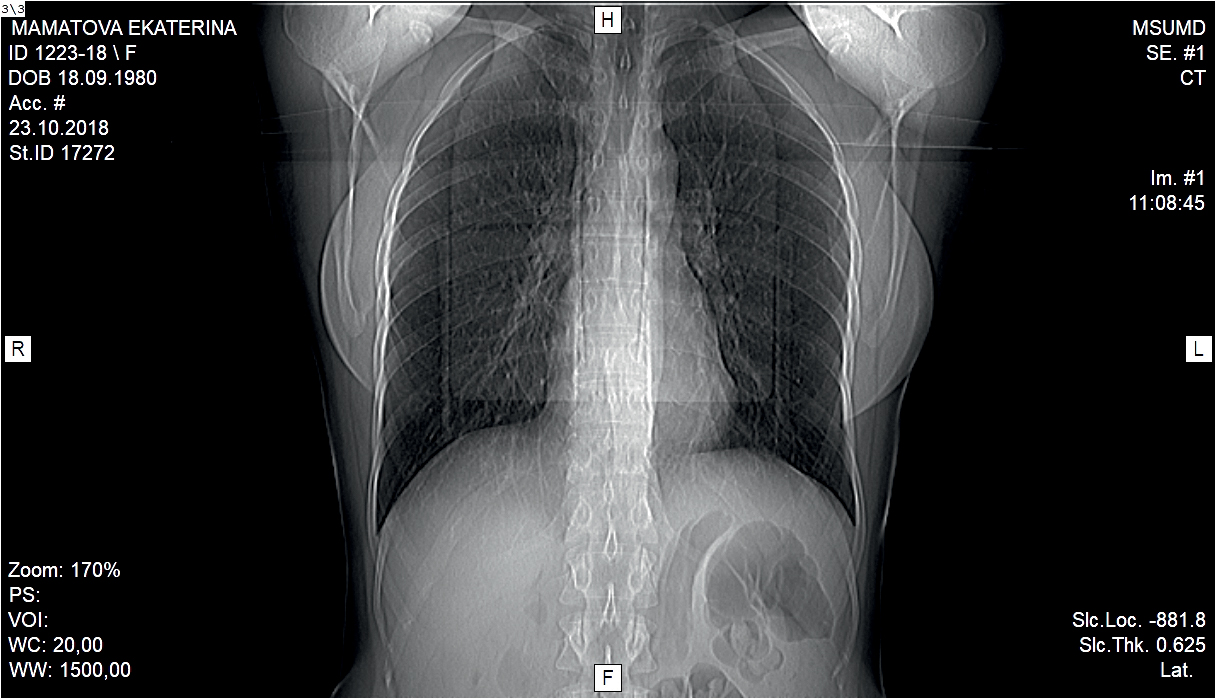

Дополнительно в октябре 2018 г. больной была проведена мультиспиральная компьютерная томография органов грудной клетки, по результатам которой были выявлены признаки интерстициальных изменений легких, измененные лимфатические узлы паратрахеальной, бифуркационной и бронхопульмональных групп (может соответствовать лимфопролиферативному процессу, саркоидозу — клинико-лабораторное сопоставление) (рис. 8).

Рис. 8. Больная М. 23.10.2018. МСКТ грудной клетки / Fig. 8. Patient M. 23.10.2018. MSCT of the chest